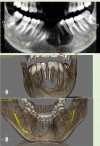

Destructive lesions in the craniofacial region especially in the jawbones, if associated with giant cells, include a spectrum of lesions that pose difficulty in diagnosis. The nature of such a lesion in the jawbones is questionable about whether it is a reactive/benign lesion or aggressive/non-aggressive. Clinical, radiological and histopathological correlation may be a reliable indicator to differentiate between the qualities of the lesion, which directly accounts for effective and individual planning of the treatment. Here we present a case of a woman in her late 20s with an unusual destructive lesion of the mandible.